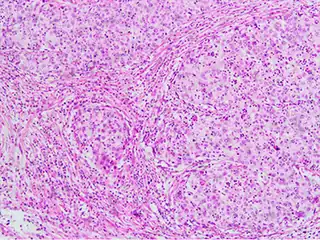

Invasive squamous cell carcinoma of the cervix is characterized by infiltration as irregular anastomosing nests or single cells.[64] This case is poorly differentiated. H&E stain.

Cervical squamous cell carcinoma generally shows diffuse staining of both nuclei and cytoplasm on p16 immuno-

histochemistry (except verrucous variant).[65]